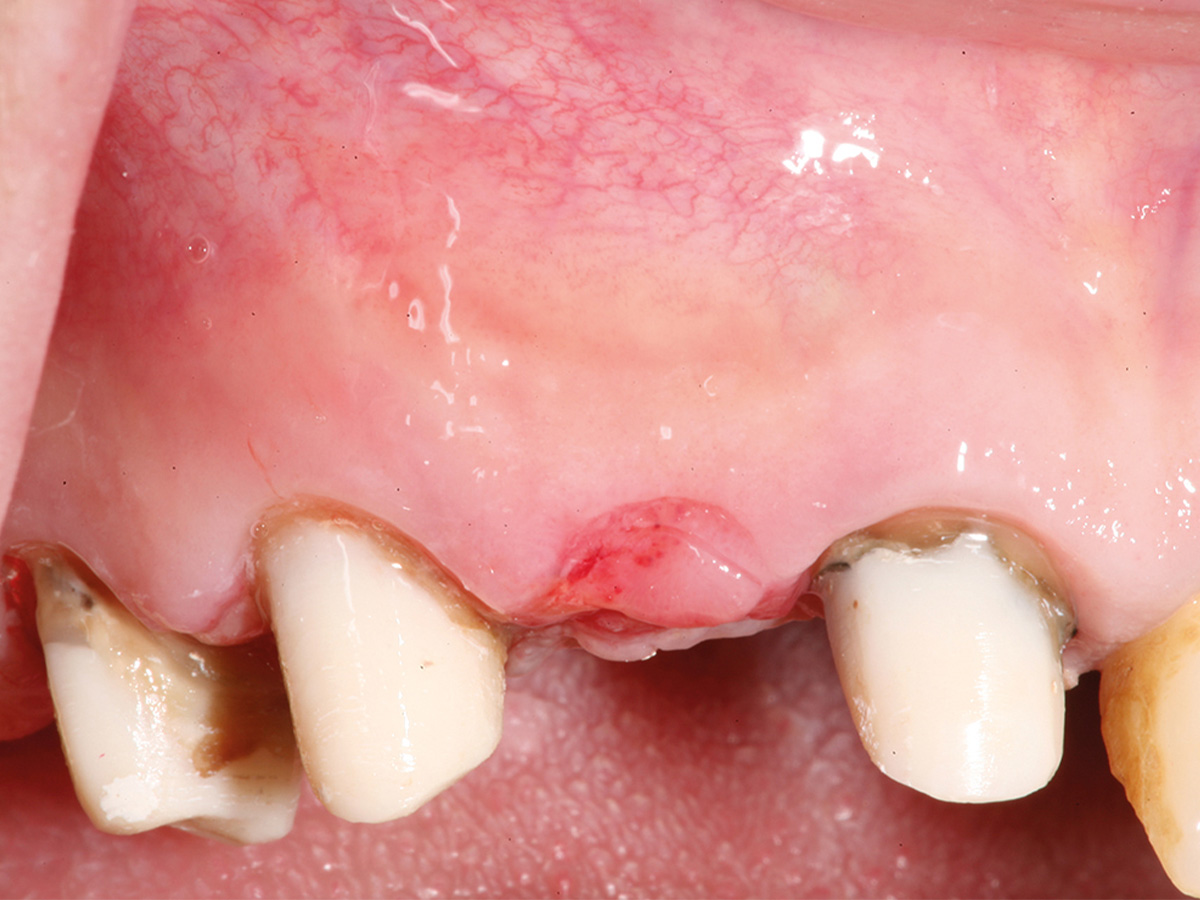

Abbildung 1

Präoperative Ausgangslage der atrophen Knochensituation mit geplantem Implantat.